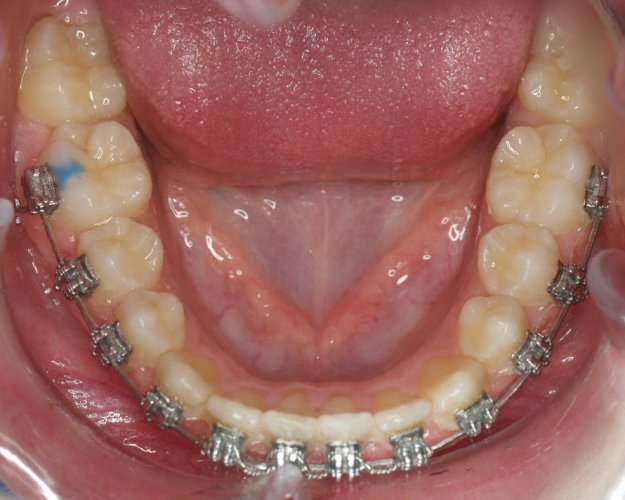

Un “diastema” es una separación extraordinariamente grande entre dos o más dientes. La mayoría de las veces, el diastema aparece entre los dos dientes delanteros superiores. Muchos niños tienen diastema cuando se les caen los dientes de leche, pero en la mayoría de los casos esta distancia desaparece cuando salen los dientes permanentes.

Los diastemas pueden deberse a una diferencia en los tamaños de los dientes, a la falta de algún diente o a que el frenillo labial sea demasiado grande. El frenillo labial es el tejido que va desde el interior del labio hasta la encía, en el lugar donde se sitúan los dos dientes delanteros superiores. Los diastemas también pueden deberse a problemas en la alineación de la boca, como la sobremordida horizontal o la protrusión de los dientes1.

- Realizar un tratamiento ortodóncico para mover los dientes y cerrar el diastema.

Si su frenillo labial es demasiado grande, puede que le remitan a un especialista para someterse a un procedimiento quirúrgico llamado frenectomía. Este procedimiento consiste en cortar el frenillo y volverlo a colocar para permitir que tenga más flexibilidad. Cuando la frenectomía se realiza en un niño, el espacio puede llegar a cerrarse por sí solo. Si se trata de un adolescente o un adulto, puede que sea necesario cerrarlo con ortodoncia. Es esencial acudir al dentista para saber cuál de estas opciones es la adecuada en su caso.